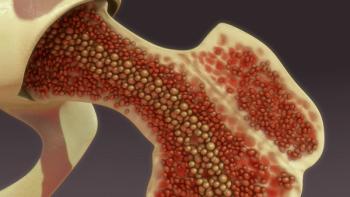

Chemo-induced myelosuppression can affect patients’ ability to do daily tasks, and management varies by patient, treatment regimens, locations, and more.